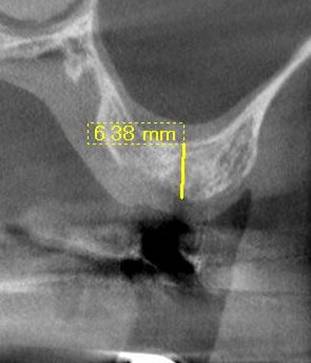

術後のCBCT

インプラントの重大な事故は下顎管から十分な距離をとれば防げます